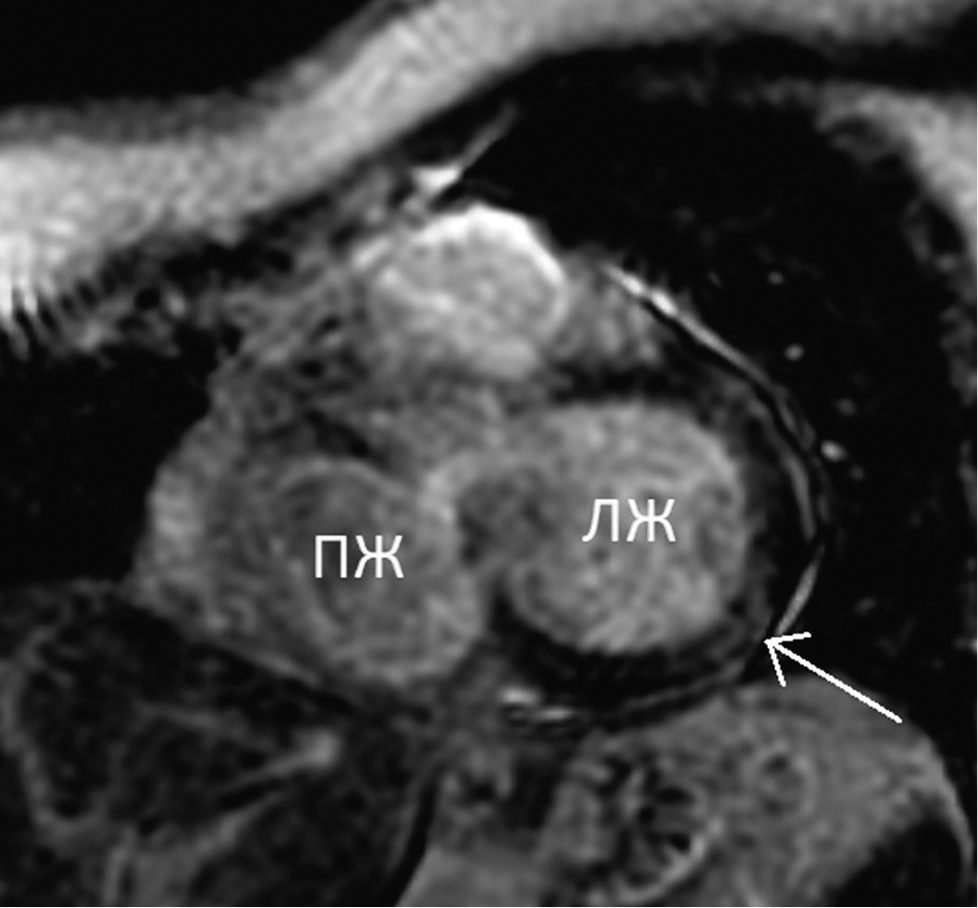

After intravenous CA administration in the delayed phase (myocardial delayed enhancement), an extended area of intramural accumulation of a nonischemic CA was identified and localized in the lower and posterolateral segments (4, 5) of the left ventricular basal sections (Figs. 4 and 5). No focal accumulation of CA was noted in areas with increased T1 relaxation time.

Fig. 4. Cardiac MRI, short axis at the level of the basal segments. Late gadolinium enhancement. The arrow indicates an intramural non-ischemic zone of contrast accumulation at the border of 4 and 5 left ventricle segments. ПЖ — right ventricle; ЛЖ — left ventricle

Рис. 4. Магнитно-резонансная томография сердца, по короткой оси на уровне базальных сегментов. Отсроченное контрастирование. Стрелкой указан интрамуральный участок накопления контрастного вещества на границе 4-го и 5-го сегментов левого желудочка неишемического характера. ПЖ — правый желудочек; ЛЖ — левый желудочек